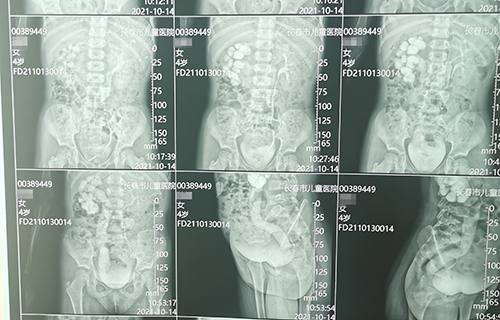

长春4岁女宝佳佳(化名)间歇性腹痛1个月,诊断为输尿管末端狭窄。这种病在儿童中发病率仅为5‰,但危害却不容小觑,长期发展会导致患侧泌尿系扩张积水,影响肾功能甚至导致肾衰竭。故一旦确诊需尽早手术治疗。那么,佳佳到底怎样了呢?

3个小时手术,完成再植

术前准备完毕。10月15日,栾志勇主任、谢方达副主任为佳佳行输尿管远端狭窄微创手术,在其肚脐周围打了3个直径5mm的小孔,在腹腔镜下顺利实施了输尿管膀胱再植。手术用时仅为3小时,出血量也比较少。

佳佳复查彩超,手术效果良好,达到出院标准。10月22日,佳佳就可以回家了。截止到目前,此类微创手术已完成8例。